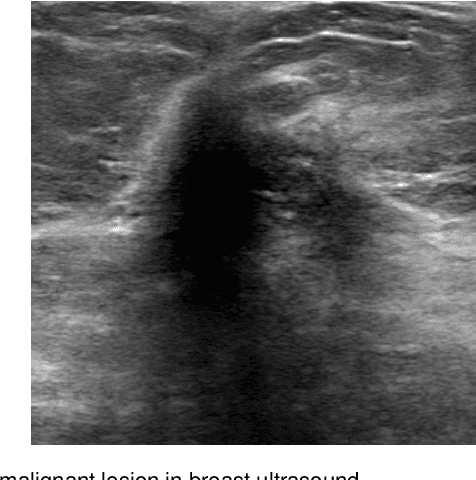

Abstract:Breast cancer is the most common invasive cancer with the highest cancer occurrence in females. Handheld ultrasound is one of the most efficient ways to identify and diagnose the breast cancer. The area and the shape information of a lesion is very helpful for clinicians to make diagnostic decisions. In this study we propose a new deep-learning scheme, semi-pixel-wise cycle generative adversarial net (SPCGAN) for segmenting the lesion in 2D ultrasound. The method takes the advantage of a fully connected convolutional neural network (FCN) and a generative adversarial net to segment a lesion by using prior knowledge. We compared the proposed method to a fully connected neural network and the level set segmentation method on a test dataset consisting of 32 malignant lesions and 109 benign lesions. Our proposed method achieved a Dice similarity coefficient (DSC) of 0.92 while FCN and the level set achieved 0.90 and 0.79 respectively. Particularly, for malignant lesions, our method increases the DSC (0.90) of the fully connected neural network to 0.93 significantly (p$<$0.001). The results show that our SPCGAN can obtain robust segmentation results and may be used to relieve the radiologists' burden for annotation.